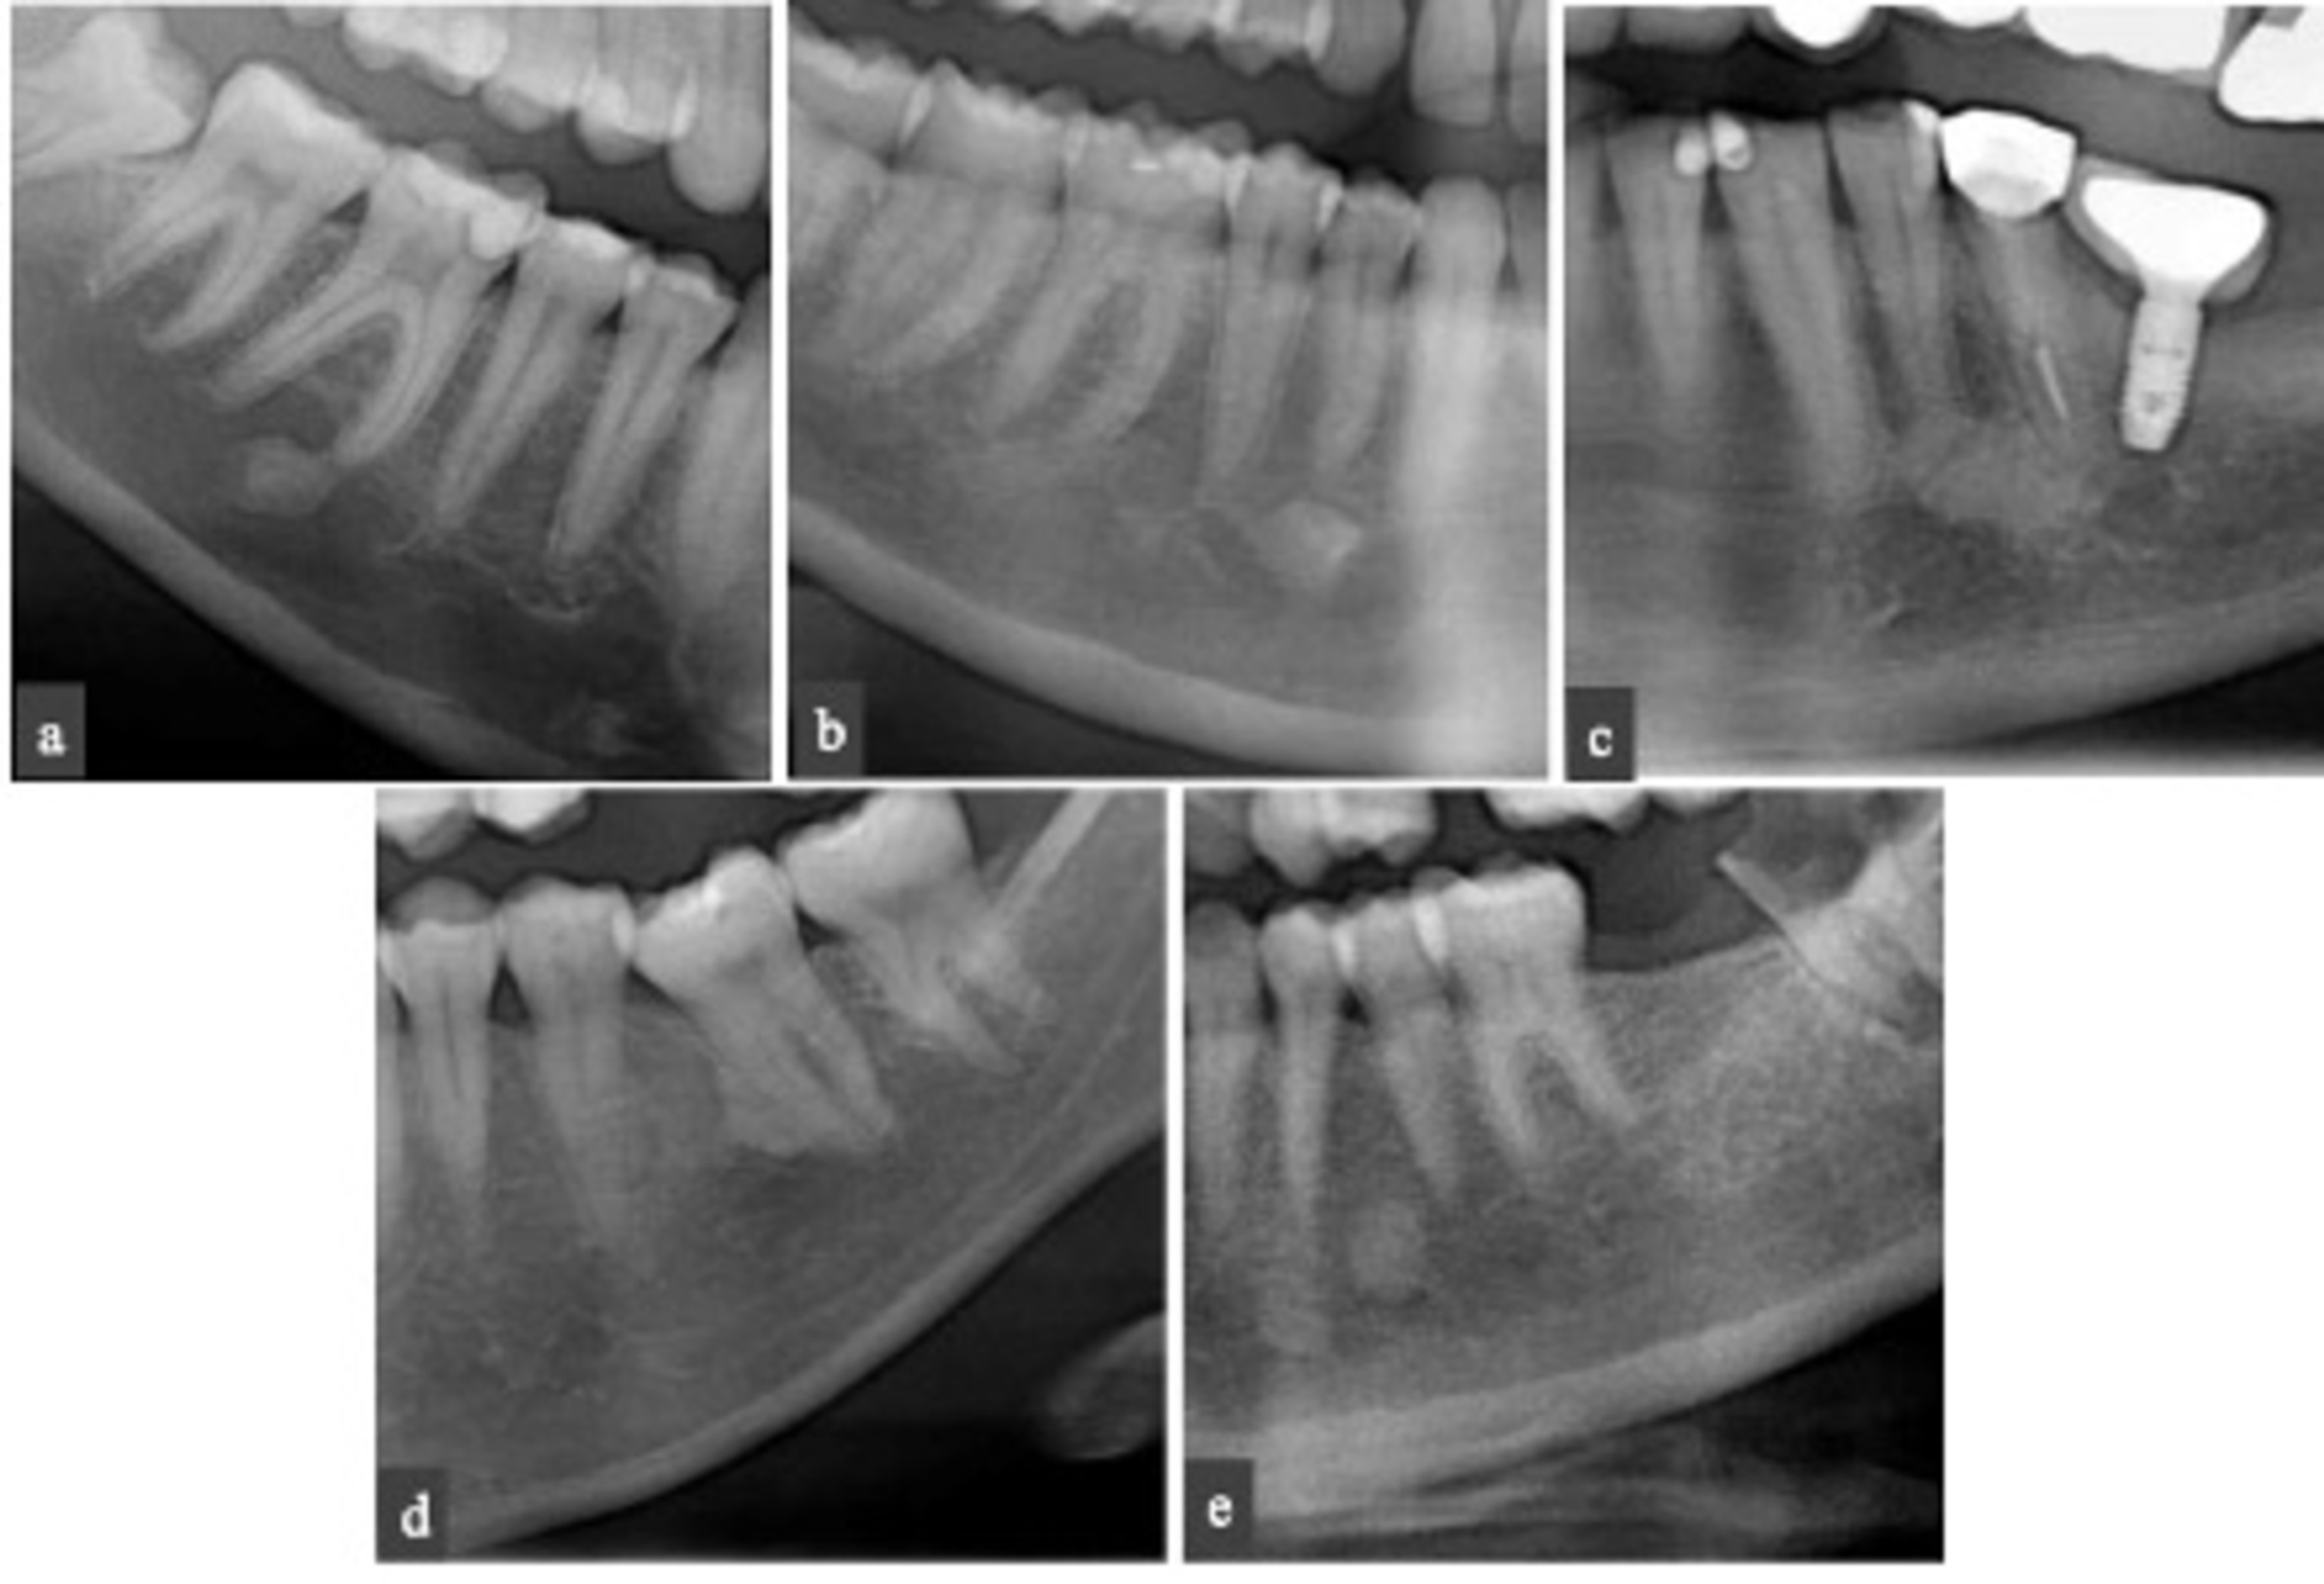

Condensing Osteitis Vital Tooth . condensing osteitis usually presents as a radiopaque area adjacent to and associated with the apex of a tooth that has either a. mandibular molars (53,23%) and premolars (43,54%) were the most frequently affected teeth, more. condensing osteitis is defined as pathologic growth of maxillomandibular bones characterized by mild clinical symptoms. on imaging, condensing osteitis is seen as a periapical, poorly marginated, nonexpansile, sclerotic lesion in the. condensing osteitis is another entity caused by chronically inflamed pulp tissue with subsequent chronic apical.

condensing osteitis is another entity caused by chronically inflamed pulp tissue with subsequent chronic apical. on imaging, condensing osteitis is seen as a periapical, poorly marginated, nonexpansile, sclerotic lesion in the. condensing osteitis is defined as pathologic growth of maxillomandibular bones characterized by mild clinical symptoms. condensing osteitis usually presents as a radiopaque area adjacent to and associated with the apex of a tooth that has either a. mandibular molars (53,23%) and premolars (43,54%) were the most frequently affected teeth, more.